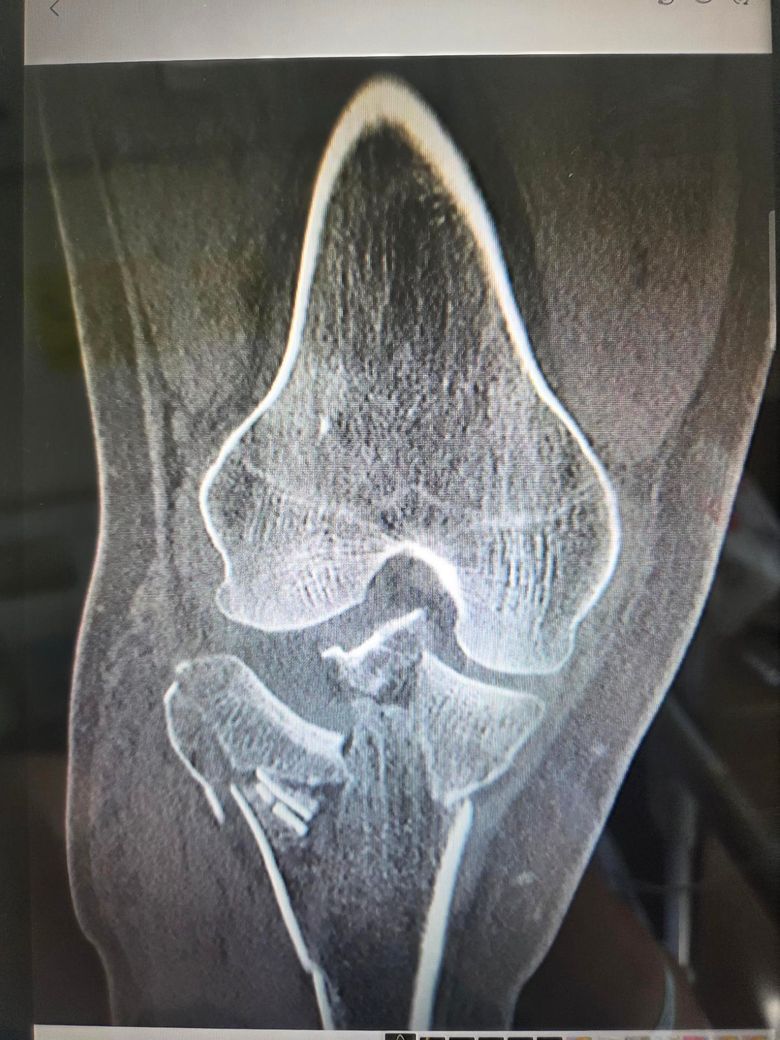

수술 후 3주차 엑스레이 사진 받아왔습니다.

• 1번 째 사진

분쇄골절 수술 후 3주차 엑스레이에서 뼈가 제 위치에 잘맞춰져 있고 금속 고정물이 안정적으로 유지된다면 수술은 성공적으로 이루어진 경우가 많습니다.

분쇄골절 이후 뼈의 정렬에 맞춰 고정이 잘 된 것으로 보이고 엑스레이상에서도 틀어짐이나 고정시 사용한 핀들이 제위치에서 크게 벗어나 있지는 않는 것으로 보입니다.

우선 현재 보여주신 엑스레이로는 분쇄 골절 된 부분은 핀으로 고정이 잘 된것으로 보여집니다.